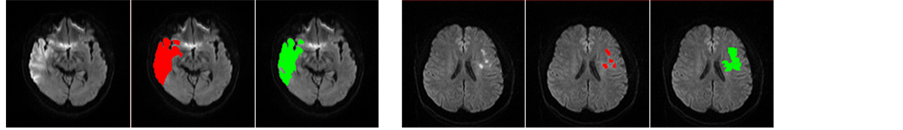

where (x0, y0) and (x, y) are symmetrical with respect to the midsagittal line (which is the intersection between the MSP and the axial slice) on the axial slice z, Ns(x0, y0) is the neighborhood of (x0, y0) and the window size of window is 5 × 5. Axial slices of B0, DWI, ADC and ASM of a patient are shown in Figure 2. It is clear that the infarct region on the right hemisphere has been enhanced to be more easily discernable than both the DWI and ADC.

Figure 2. From left to right, axial slices of B0, DWI, ADC and ASM.